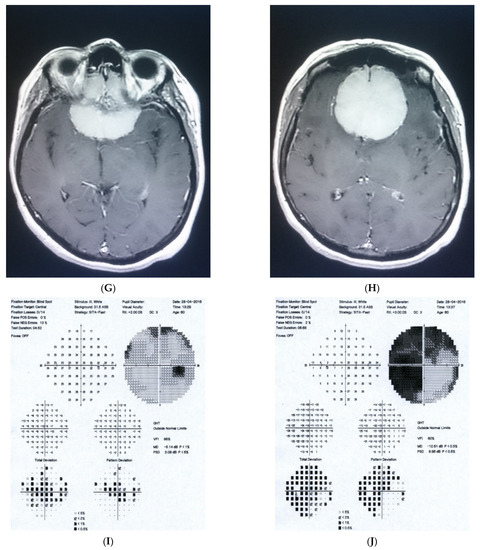

2.2. Case 2

2.3. Case 3